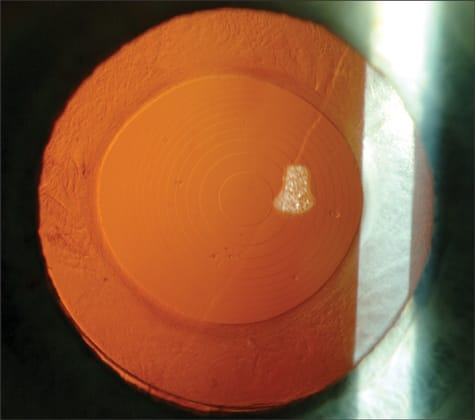

Figure 1. Slit-lamp photograph of a ReStor lens.